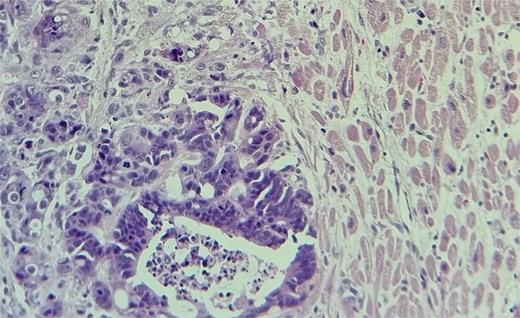

The metastatic tumor cells form glandular structures and infiltrate the myocardial tissue in a disorganized manner.

Subsequent echocardiography showed an ejection fraction of 70%, normal left ventricle dimensions, grade II left ventricular diastolic dysfunction, and a mass attached to the right ventricular wall. Mild pulmonary hypertension was noted. The patient underwent an open-heart procedure via median sternotomy under cardiopulmonary bypass. The tumor was adherent to the right ventricular wall, necessitating meticulous dissection to preserve myocardial integrity. The mass was excised completely, and histopathological examination confirmed metastatic adenocarcinoma consistent with a colon primary (Figs 4 and 5). Postoperatively, the patient initially showed stable cardiac function with preserved ejection fraction.